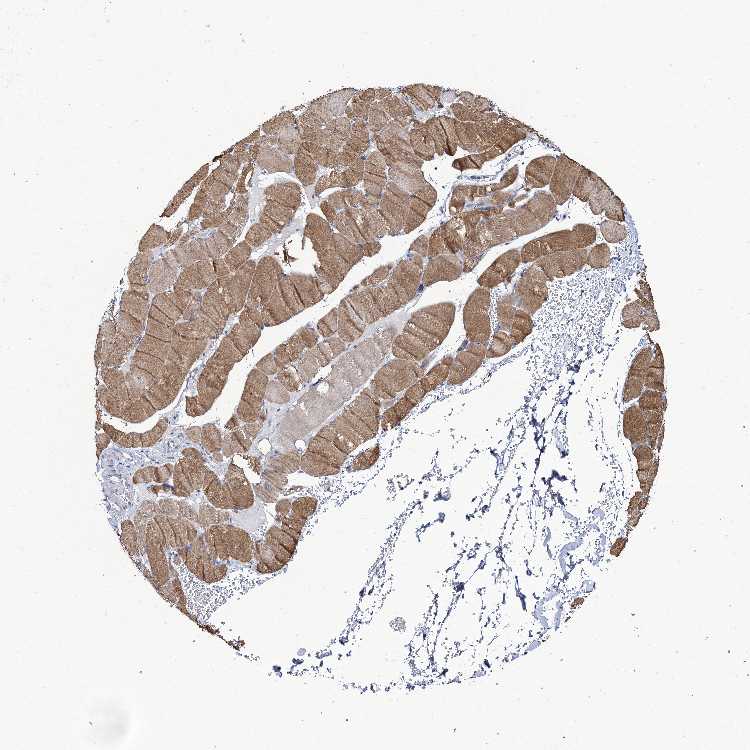

SOFT TISSUE 1 - Antibody stainingi

Antibody staining in the annotated cell types in the current human tissue is reported as not detected, low, medium, or high, based on conventional immunohistochemistry profiling in selected tissues. This score is based on the combination of the staining intensity and fraction of stained cells.

Each image is clickable and will lead to virtual microscopy that enables deeper exploration of all samples and also displays staining intensity scores, fraction scores and subcellular localization as well as patient and tissue information for each sample.

Antibody HPA039117

Fibroblasts Low

Peripheral nerve Not detected